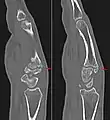

1. Conway, William F.; et al. (1984). "The Carpal Boss: An Overview of Radiographic Evaluation" (PDF). Radiology. 156 (1): 29–31. doi:10.1148/radiology.156.1.3923555. PMID 3923555. Retrieved 27 July 2020.

3. Conway, W.F. "The carpal boss: an overview of radiographic evaluation". Radiological Society of North American. Retrieved April 13, 2020.